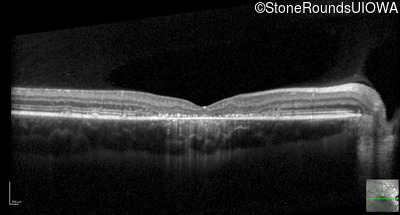

Optical Coherence Tomography - Right - 20/80 -1

Exemplar / OCT Stack

OCT Stack